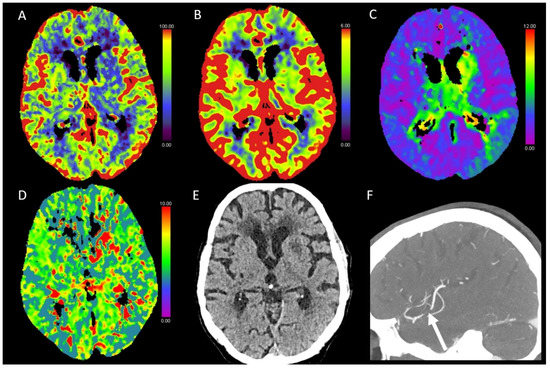

3.6. Vasospasm

3.9. Veneous Thrombosis